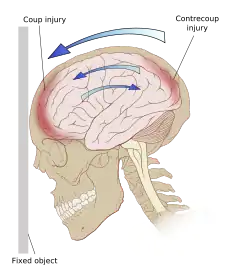

Even in the absence of an impact, significant acceleration or deceleration of the head can cause TBI; however in most cases, a combination of impact and acceleration is probably to blame.[37] Forces involving the head striking or being struck by something, termed contact or impact loading, are the cause of most focal injuries, and movement of the brain within the skull, termed noncontact or inertial loading, usually causes diffuse injuries.[20] The violent shaking of an infant that causes shaken baby syndrome commonly manifests as diffuse injury.[67] In impact loading, the force sends shock waves through the skull and brain, resulting in tissue damage.[37] Shock waves caused by penetrating injuries can also destroy tissue along the path of a projectile, compounding the damage caused by the missile itself.[23]

Damage may occur directly under the site of impact, or it may occur on the side opposite the impact (coup and contrecoup injury, respectively).[66] When a moving object impacts the stationary head, coup injuries are typical,[68] while contrecoup injuries are usually produced when the moving head strikes a stationary object.[69]